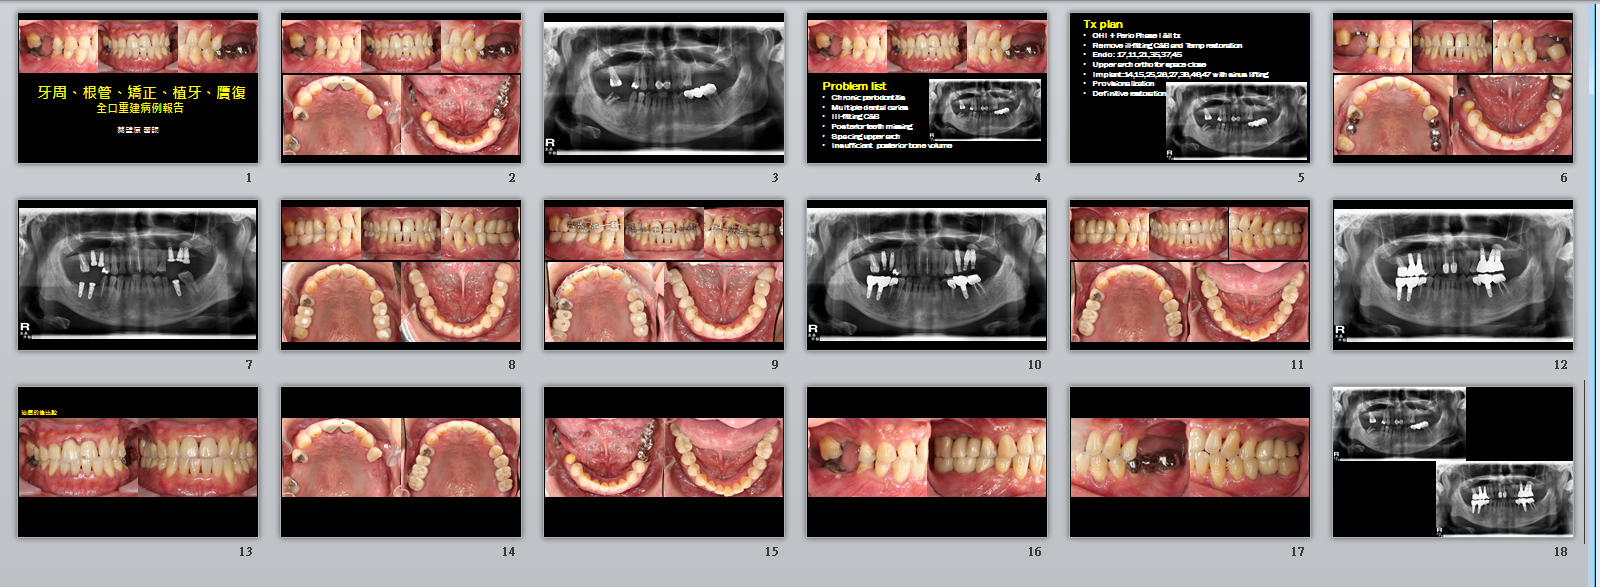

治療前的口內照片

經過資料收集,問題評估階段,我們擬定適當的治療計畫,並告知所需的費用才開始整體治療。我們重視的刷牙這位病人確實做的很好,一邊拆除不良假牙,重新根管治療,一邊進行植牙手術,並更換成臨牙假牙。對於前牙空間過多,我們建議利用矯正關閉多餘的空間,後方的植牙也提供錨定功能,幫助前牙空間關閉。整體牙周狀況逐漸改善,病人慢慢體會到其實這樣的治療方向才是正確的。

治療之後口內照片

經過九個多月的治療,病人重拾咀嚼的快樂與前牙美觀性假牙,牙周不流血發炎,之後每半年的定期檢查,我們很開心病人可以得到這樣的結果。

全口重建詳細的治療步驟